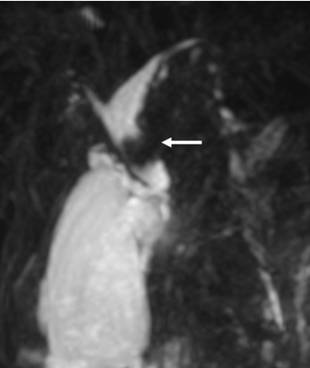

По клинической симптоматике пациенты были разделены на две группы: ,40%) – с синдромом болевой механической желтухи,,60%) – с синдромом безболевой механической желтухи. Причинами обтурационной желтухи у ,91%) пациентов явились: желчнокаменная болезнь, холедохолитиаз (Рис. 1), у,73%) – заболевания (опухолевые и неопухолевые) желчных протоков, прочие болезни панкреатобилиарной зоны, вызывающие внешнюю компрессию желчных протоков (Рис. 2), составили 30,36% (75 больных). (табл. 1).

Рис. 1 МРХПГ. Конкремент в общем печеночном протоке.